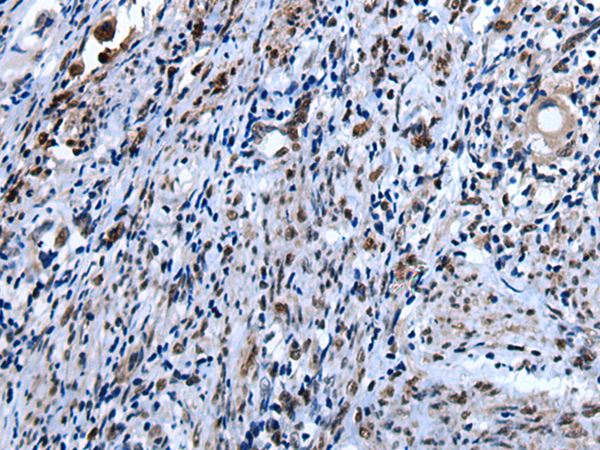

ELISA, IHC |

IHC positive control: |

Human colorectal cancer and human cervical cancer |

IHC Recommend dilution: |

25-100 |